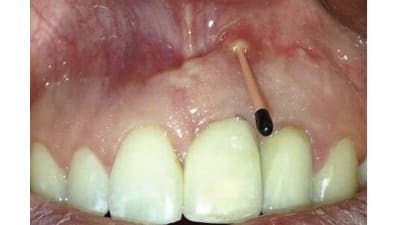

In this clinical case series, two patients with different presentations of RPI were treated with guided bone regeneration (GBR) using bone graft and collagen membrane.

Within the limitations of this case report, the biomaterial demonstrated efficacy, clinical manageability, and costeffectiveness as a single-modality approach, reducing the need for additional interventions.